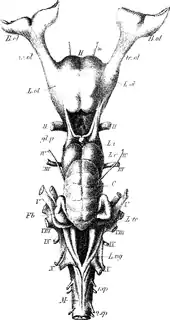

Three forms of the nerve on the underside of human brains

Three forms of the nerve on the underside of human brains Brain viewed from below. Gyrus rectus seen at anterior centre.

Brain viewed from below. Gyrus rectus seen at anterior centre.